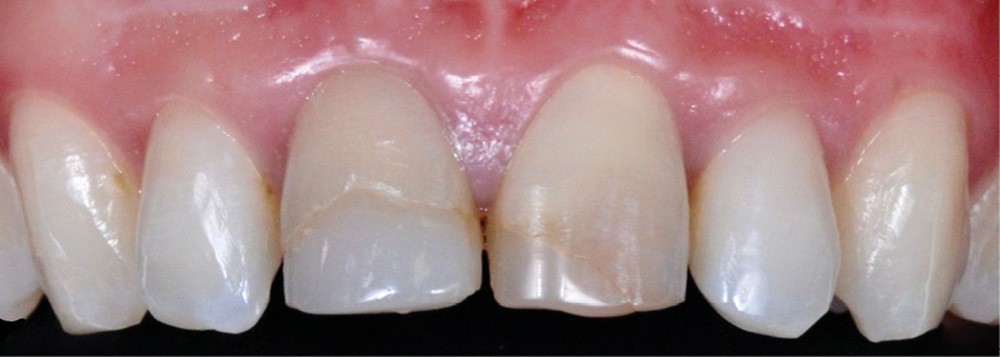

– la nécrose, qui va donner une coloration plutôt brune [3] (fig. 1, 2) ;

– le trauma, qui va donner une couleur plutôt rouge [4] (fig. 3) ;